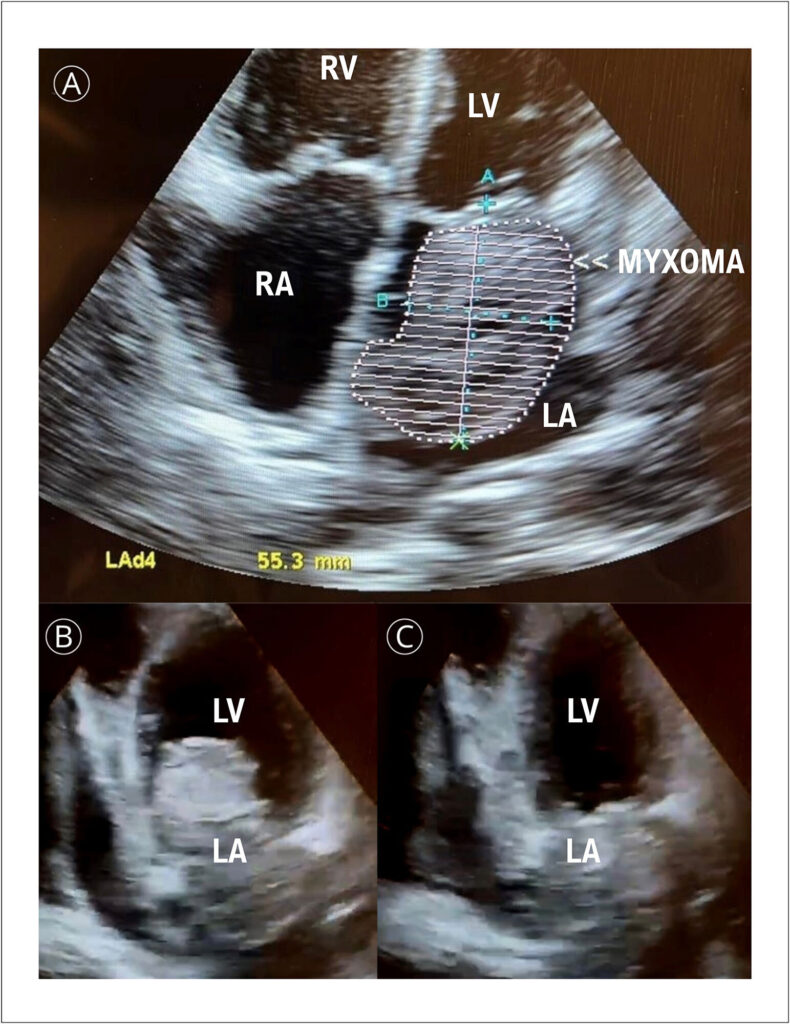

Atrial Myxoma in Male Young Adult Patient: A Case Report and Literature Review

Cardiac tumors are found in 0.001% to 0.3% of autopsies, where myxoma is the most common cardiac neoplasia. Approximately 70% appear in the left atrium next to the foramen ovale and are pedunculated. Its pedunculus can be short, limiting its movement, or can be long, allowing tumor movement inside and outside the atrium during the cardiac cycle.,

Clinical conditions depend on the size, mobility, and location of the tumor. Classic symptoms are related to Goodwin’s triad, which includes unspecific systemic symptoms, embolism and intracardiac obstruction. Among systemic symptoms are dyspnea, orthopnea, paroxysmal nocturnal dyspnea, pulmonary edema, cough, hemoptysis, edema, and fatigue due to obstructive features of neoplasia.,